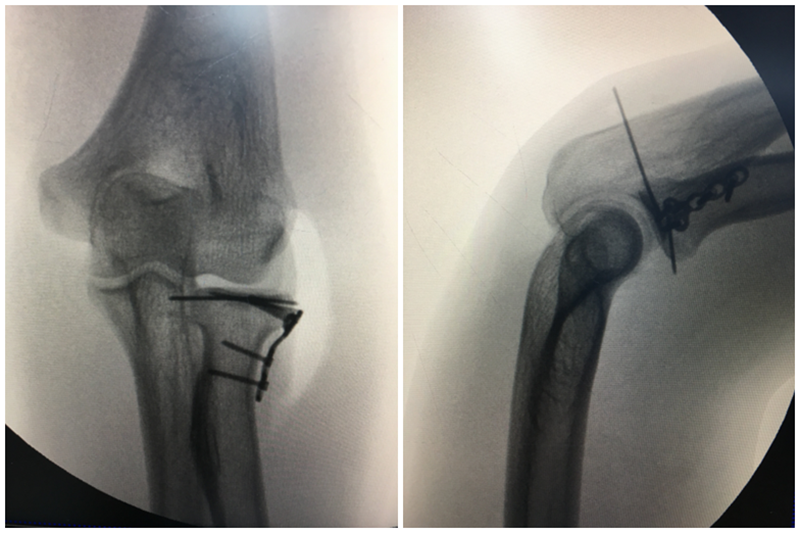

①1.0mm克针或2.7mm螺钉固定,骨折复位巾钳固定,保持骨折块血运,关节面解剖复位,内固定。应旋后位,克针从骨折块前半部打入;然后旋前位,克针从骨折块后半部打入。用手动埋头器磨出埋头孔。再拧入螺钉。与骨折面垂直固定,经桡骨头非关节面穿钉。

注意:钉帽在非关节边缘;螺丝钉垂直于骨折线;螺丝钉远端不与尺骨关节面接触。

③ L型钢板固定

前臂中立位,桡骨小头外后40°扇形,为最佳钢板放置安全区,适合于粉碎骨折。

前臂旋转中立位时,桡骨头切面10点(左侧10点,右侧2点)为中心的110°弧形范围为钢板放置相对安全区。

图6 桡骨头内固定安全区

桡骨头边缘的前外1/3缺少关节软骨,且在旋转时不会撞击尺骨的桡骨切迹,适合于放置内固定。微型钢板型边缘平行于环形关节面,并低于软骨面1~2mm。桡骨小头近端为一凹陷关节面,坡度20~30°,螺丝钉方向向近侧倾斜20~30°。

图9 骨折固定